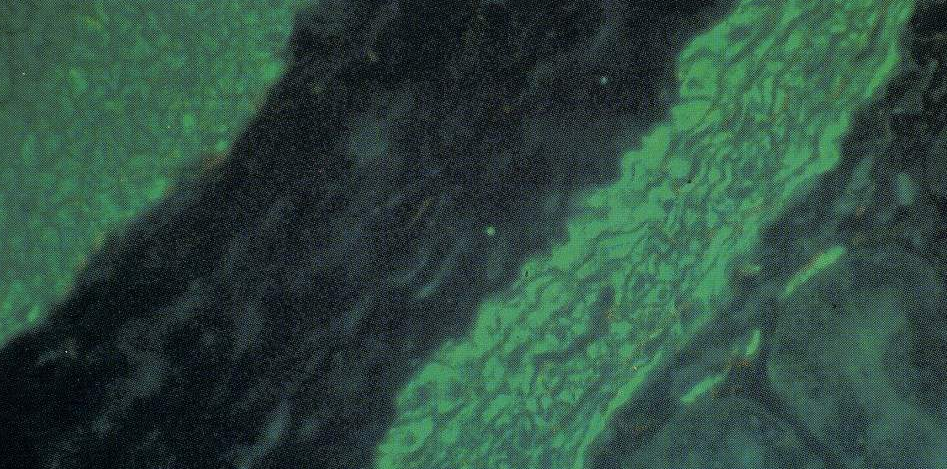

Les complexes sont identifiés grâce à leur localisation précise au niveau des structures du substrat. Ce dernier est constitué de foie de rat et/ou de cellules Hep2 pour les AAN, rein de rat pour les AAM et estomac de rat pour les AML (Fig 1 et 2).

Fig.1 : AAN positifs sur des coupes de foie de rat.

Fig.2 : AML positifs sur des coupes d’estomac de rat.